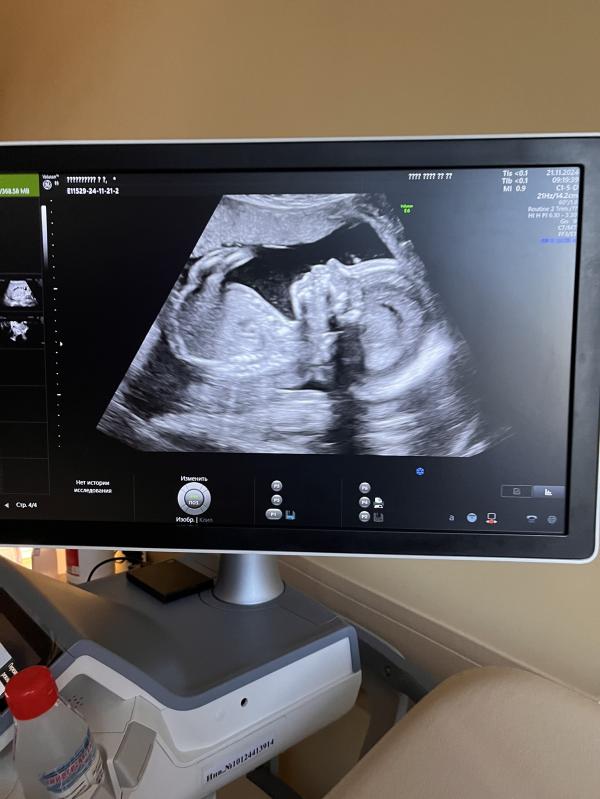

Всем привет. Сегодня была на 2-ом скрининге, напугали… сказали носик не дотягивает до нормы и отправили на дообследование, чтобы исключить патологии.

Такой красавчик!носик симпатичный такой. Я бы не прокалывала. Тоже бы очень боялась. Тем более на новом скрининге все было идеально

Хорошенький носик , какое чудо , не переживайте..мне в 3 беременность тоже сказали на 1 скрининге , что маленький нос . Ничего страшного , ребёнок родился все хорошо. Пусть все будет хорошо, берегите себя и малыша

Из за одного носа не надо прокалывать живот, тем более 5,3 это нормальный размер, у нас 4,4 мм вообще на 2 скрининге косточка эта, я прочитала много историй что это особенность ребенка, сдала НИПТ на синдром дауна и успокоилась.